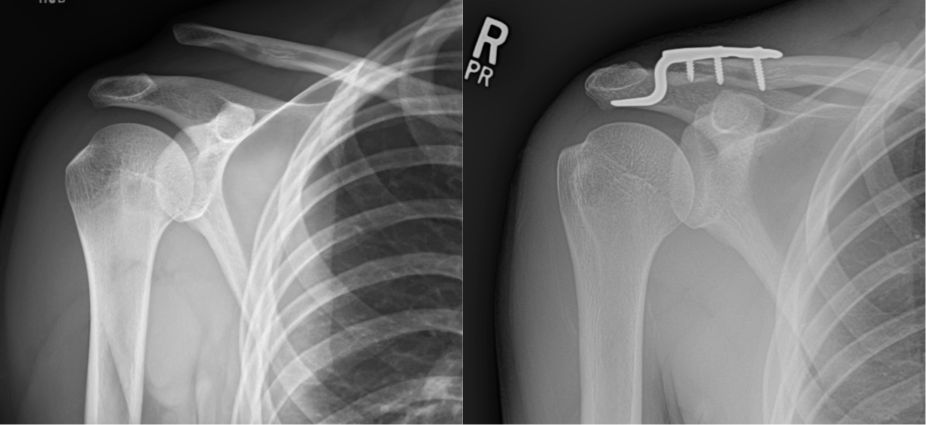

A direct fall on the shoulder can cause a "shoulder separation" or acromioclavicular (AC) joint sprain. This injury is usually sports related. Some separations happen in car accidents or falls. This is not the same as a shoulder dislocation, which occurs at the large joint where the arm attaches to the shoulder, although the two may appear to be the same.

The shoulder separation, or acromioclavicular (AC) dislocation, is an injury to the junction between the collarbone and the shoulder. It is usually a soft-tissue or ligament injury but may include a fracture (broken bone).

High grade sprains can result in elevation of the distal end of the clavicle resulting in a bump or prominence. These are usually treated without surgery. If significant displacement or pain persists after non-operative treatment, surgical repair can be performed. Acute injuries can be treated with plating or other fixation methods, whereas chronic tears require ligament reconstruction.

Shoulder radiographs demonstrating a "shoulder separation" or acromioclavicular sprain ("AC sprain"), with the clavicle end elevated away from the acromion (left image), and repair with open reduction internal fixation (right image).